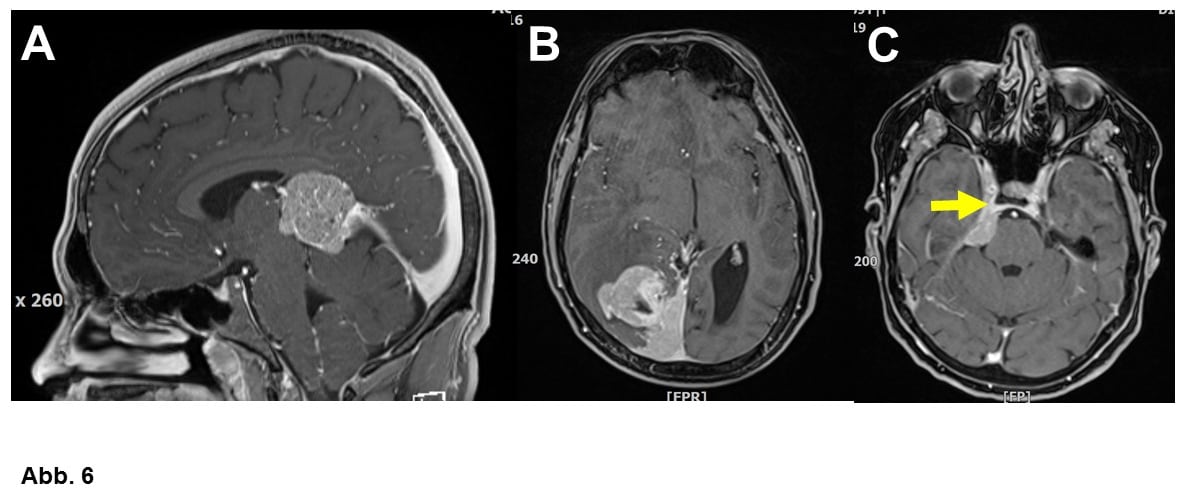

Ca. 10 bis 20% aller Meningeome wachsen überdurchschnittlich schnell bzw. häufig trotz Behandlung wieder nach. Die Neuropathologie unterscheidet zwischen den häufigen WHO-Grad I (gutartig), den selteneren WHO Grad II (Abb. 4B und 6A) und den sehr seltenen und klinisch bösartigen anaplastischen Meningeomen WHO Grad III (Abb. 6B). Es gibt verschiedene histologische Typen (= unterschiedliche Erscheinungsbilder unter dem Mikroskop), was aber meist für die Klinik keine Rolle spielt. Einige wenige Tumoren werden allerdings aufgrund ihrer Histologie den WHO Graden II oder sogar III zugeordnet.

Als Standardbehandlung gilt die Operation. Ziel ist die komplette Entfernung des Tumors inklusive seines Ansatzes im Bereich der Hirnhäute und eines eventuell vom Meningeom auch befallenden Knochens, wobei man natürlich das hiermit verbundene OP-Risiko gegen den Nutzen abzuwägen hat (Abb. 1-5). Deswegen ist es in manchen Fällen durchaus angebracht, ein Meningeom nicht radikal zu operieren (Abb. 6C).

Letztlich sind alle Meningeome strahlensensibel, wobei aber die Strahlentherapie umso besser wirkt, je schneller der Tumor wächst bzw. umso bösartiger er ist. Deswegen sollen WHO Grad III-Meningeome alle nach der Operation bestrahlt werden (Abb. 6B). Bei WHO Grad II-Meningeomen ist die Frage der postoperativen Strahlentherapie Gegenstand von klinischen Studien. Einen auch im MRT sichtbaren Tumorrest, den man nicht operieren will oder kann, sollte man vermutlich bestrahlen (vgl. Abb. 6A). WHO Grad I-Meningeome werden in der Regel nur dann bestrahlt, wenn sie wachsen und nicht operabel sind. Kleine Tumoren oder Tumorreste können je nach Lage häufig mit sehr gutem Erfolg strahlenchirurgisch behandelt werden. Das spielt v.a. bei Schädelbasistumoren eine sehr große Rolle (Abb. 6C).

A. 20-jähriger Patient mit einem atypischen Meningeom WHO-Grad II. Hier gelang trotz der schwierigen Lage eine Komplettentfernung, so dass man auf eine Nachbestrahlung verzichten konnte.

B. Bösartiges WHO-Grad III-Meningeom bei einem 55-jährigen Mann. Hier sollte man unbedingt nach der Operation bestrahlen.

C. 69-jährige Frau mit Gesichtsschmerzen und einem WHO-Grad I-Meningeom. Die meisten Neurochirurgen würden nur einen Teil dieses Tumors entfernen und den Rest (Pfeil) oder vielleicht sogar den ganzen Tumor bestrahlen lassen bzw. radiochirurgisch behandeln.